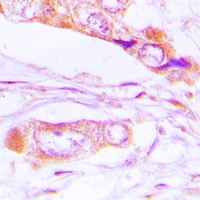

ERK1/2 (Phospho-T202/Y204) Antibody抗体

ERK1/2 (Phospho-T202/Y204) Antibody

IHC, WB

应用稀释比例:WB: 1-500:1000, IHC-P: 1-100:200